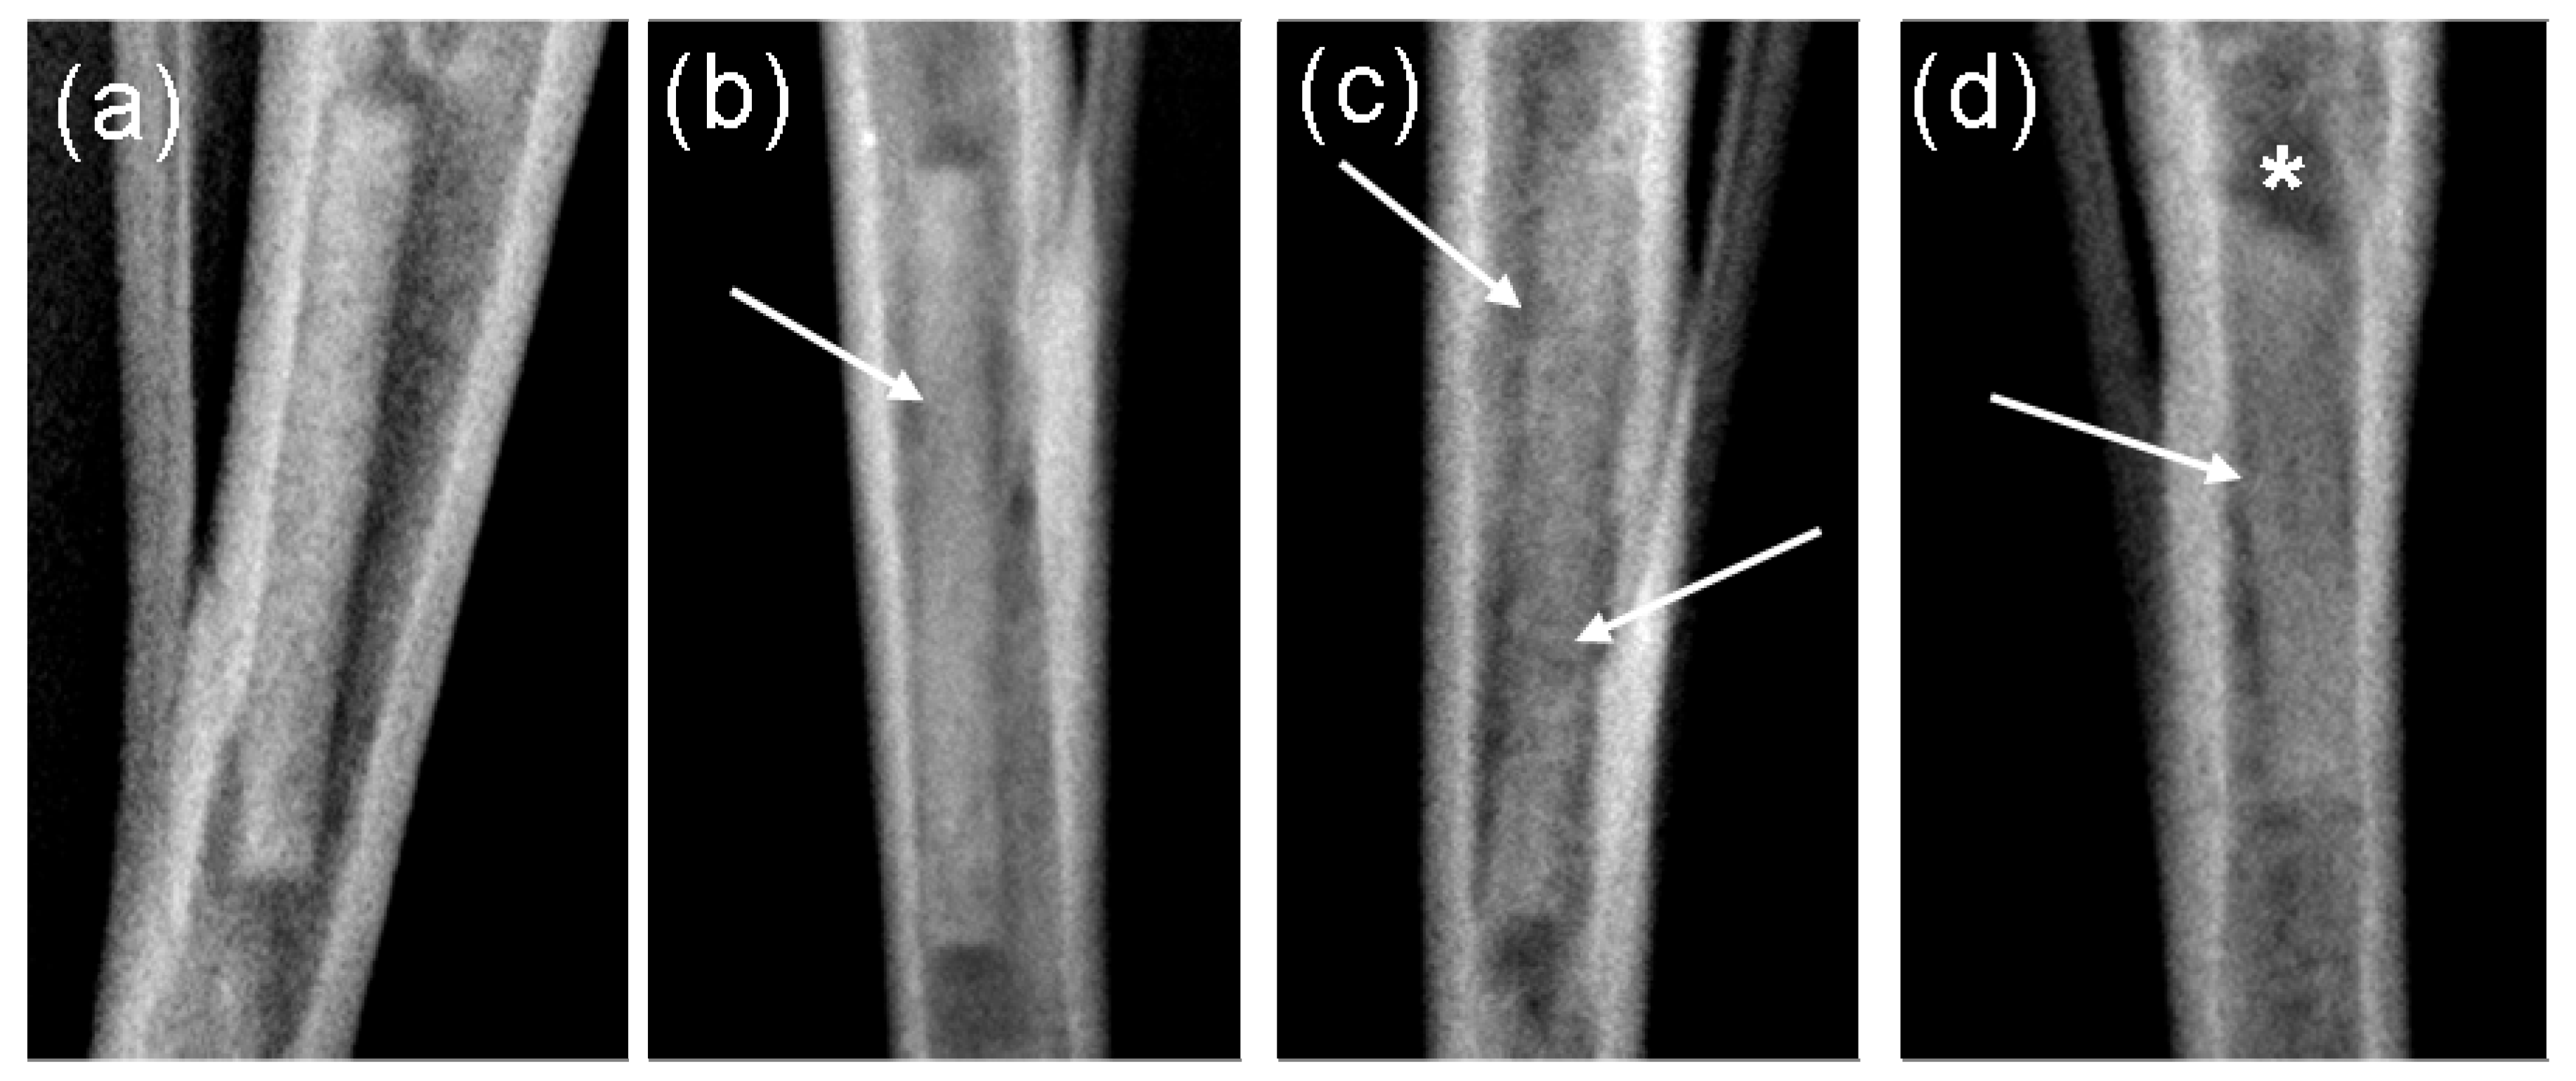

2.2. Radiological Investigations

2.3. µ-Computed Tomographic Investigation of the in Vivo LANd442-Pins

3.2.4. Radiological Investigation

3.2.5. In Vivo µ-Computed Tomography